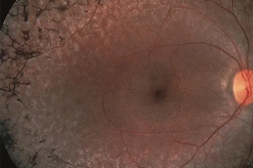

Retina treatment encompasses a range of medical interventions aimed at preserving or restoring vision compromised by retinal disorders. The retina, a delicate layer of tissue at the back of the eye, plays a crucial role in vision by converting light into neural signals that are sent to the brain. When the retina is damaged or affected by disease, it can result in vision loss or impairment. Fortunately, advancements in medical technology and treatment options offer hope to those suffering from retinal conditions.

A retinal examination — sometimes called ophthalmoscopy or funduscopy — allows your doctor to evaluate the back of your eye, including your retina, optic disk and the underlying layer of blood vessels that nourish the retina (choroid). Usually before your doctor can see these structures, your pupils must be dilated with eye drops that keep the pupil from getting smaller when your doctor shines light into the eye.